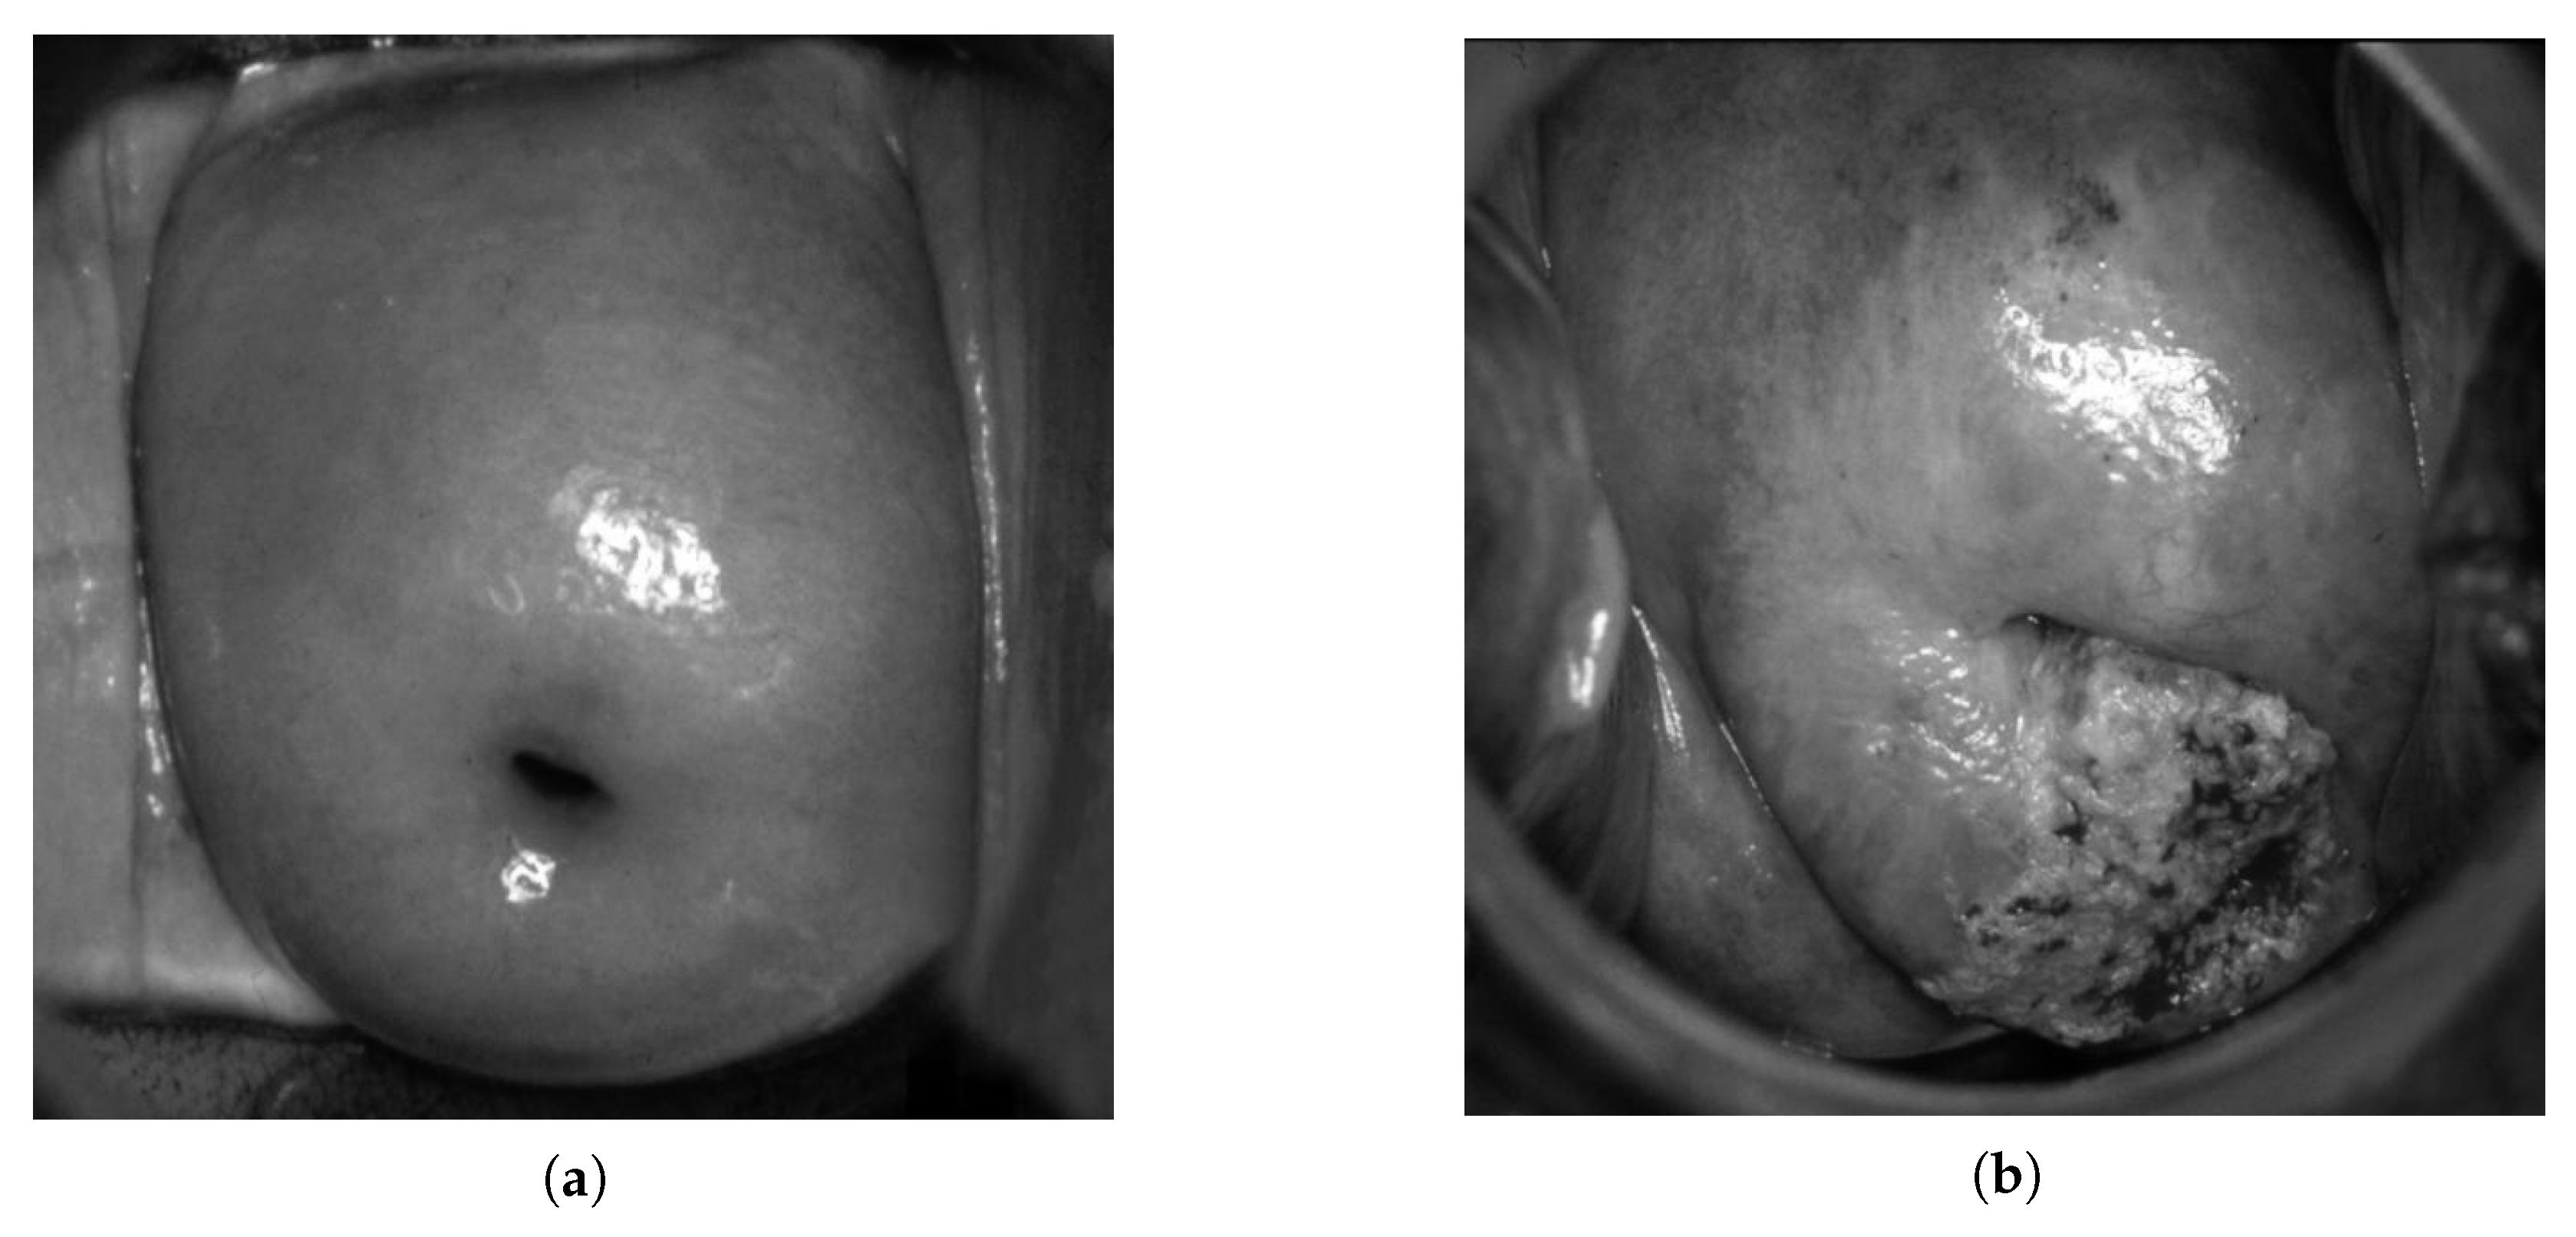

- An image is converted into grayscale;

- A grayscale image binarization is performed to select glares;